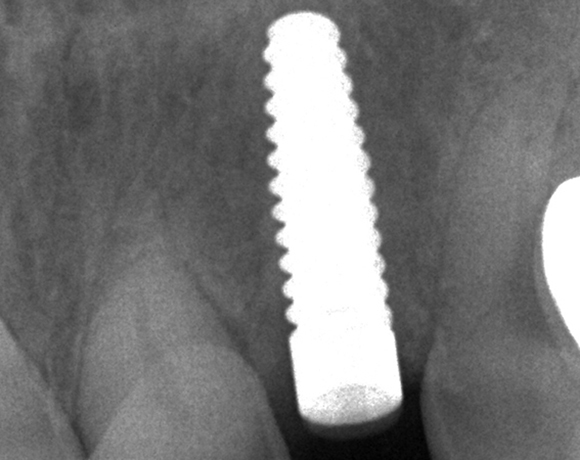

Zeramex T Implantat für Zahn 22

Einzelimplantate in der Front stellen oft ein Problem dar. Zirkonimplantate im Gegensatz zu Titanimplantate machen ästhetisch weniger Probleme, durch die weisse Farbe passen sie sich besser an das Zahnfleisch an.

Ein Projekt aus dem Jahr 2013

Im vorliegenden Patientenfall musste der Zahn 22 nach erfolgloser Endodontie entfernt werden. Die Nachbarzähne waren kariesfrei, es wurde eine Marylandbrücke (eine Brücke mit zwei Flügelchen, die palatinal an den Nachbarzähnen verklebt werden) oder ein Implantat besprochen. Die Patientin hat sich für ein Vollkeramikimplantat entschieden. In der Diashow wird der operative Eingriff bis zur fertigen Krone gezeigt. Die Einheilzeit betrug drei Monate.